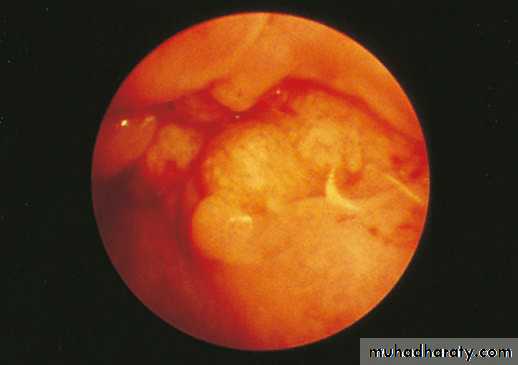

Endoscopy is the best tool for diagnosing esophageal tumors, the only limitation is that only the mucosal surface is biopsied and studied, so other investigations may be needed eg EUS, CT scan.Bronchoscopy : used for diagnosis of upper two-thirds of esophageal tumors. Cause 30% of esophageal tumors have local invasion to the trachea.

figure 3:Endoscopic appearances of a mid-oesophageal Squamous cell carcinoma